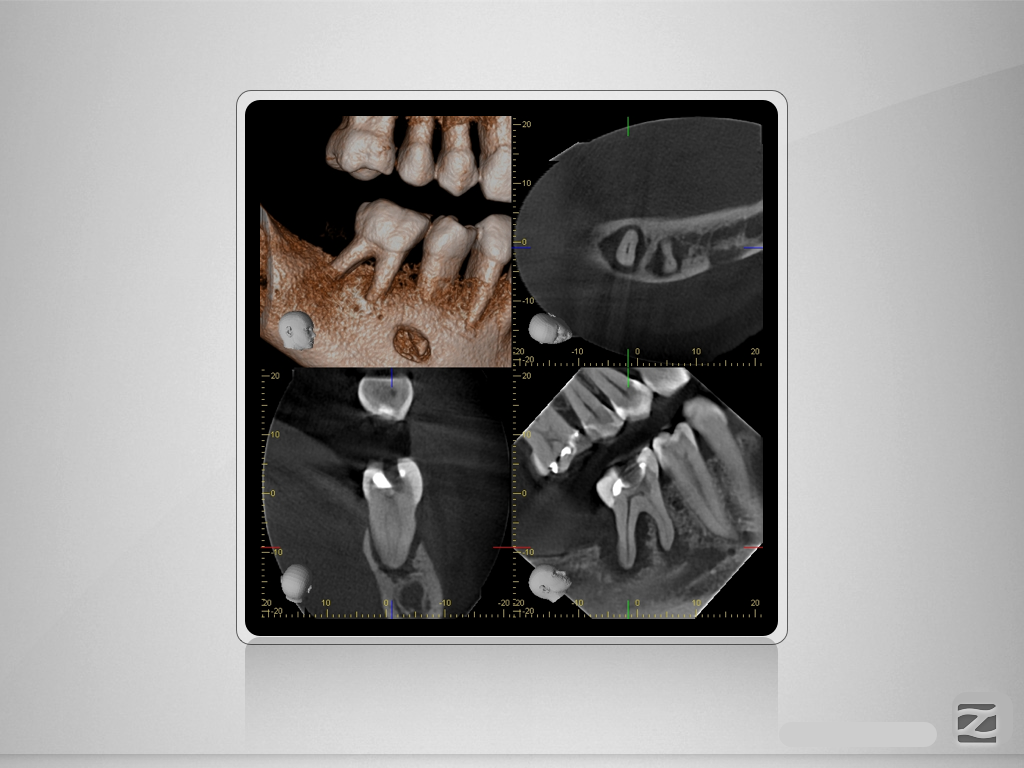

46D.002

Für oder Wider?